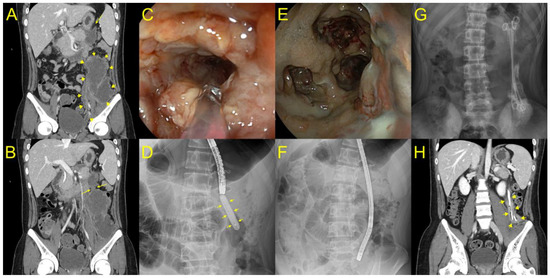

Figure 3. A case of elongated WON extended to the left paracolic gutter. (A,B) Computed tomography showing that an elongated WON (yellow arrow) extended to the left paracolic gutter was concatenated with the stomach. (CE) A gastroscope was inserted into the proximal portion of the cavity through a lumen-apposing metal stent (LAMS), and we found a long narrowing WON endoscopically and radiologically. (F) After DEN, three plastic stents with double pigtail configuration remained in place through LAMS to the deep portion of WON until the next session of DEN. (G) After nine DEN procedures, long plastic stents remained in the deep portion of WON with partial improvement radiologically. (H) After 11 DEN sessions, where the long plastic stents remained in the deep portion of WON, the patient recovered with complete WON resolution (yellow arrow).